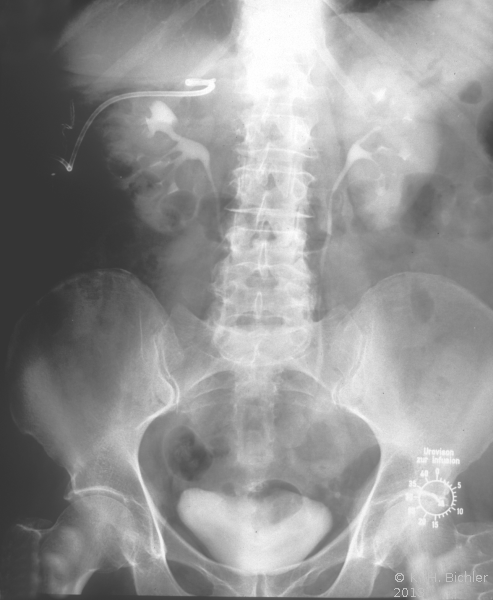

Die Patientin wurde beim Urologen wegen seit 3 Wochen persistierender Flankenschmerzen rechts vorstellig. Der Untersuchungsbefund zeigte als Auffälligkeit ein klopf- und druckschmerzhaftes Nierenlager rechts. Der Urinstatus wies keine Besonderheiten auf. Sonographisch fand der Urologe eine ca. 11 cm große einfache Nierenzyste rechts, die bis in das Nierenbecken reichte. Mit dem anschließend durchgeführten i.v.-Pyelogramm konnte eine Abflussbehinderung aus dem Nierenhohlraumsystem ausgeschlossen werden. Es waren jedoch glatt berandete, zystentypische Kelchausziehungen der oberen und mittleren Kelchgruppe zu erkennen. Der Urologe stellte die Patientin stationär in der Klinik vor. Zum Ausschluss eines eventuell vorliegenden zystischen Karzinoms wurde ein CT des Abdomens durchgeführt. Hier fand sich eine große, unkomplizierte Zyste, die die Niere verdrängte (Abbildung 4).

Symptomatische und komplizierte Zysten bedürfen einer eingehenden Abklärung und entsprechender Therapie. Bei Tumorverdacht sollte die Nierenfreilegung zur Histologiegewinnung erfolgen (Bosnik III/IV) (s. Abbildung 3).